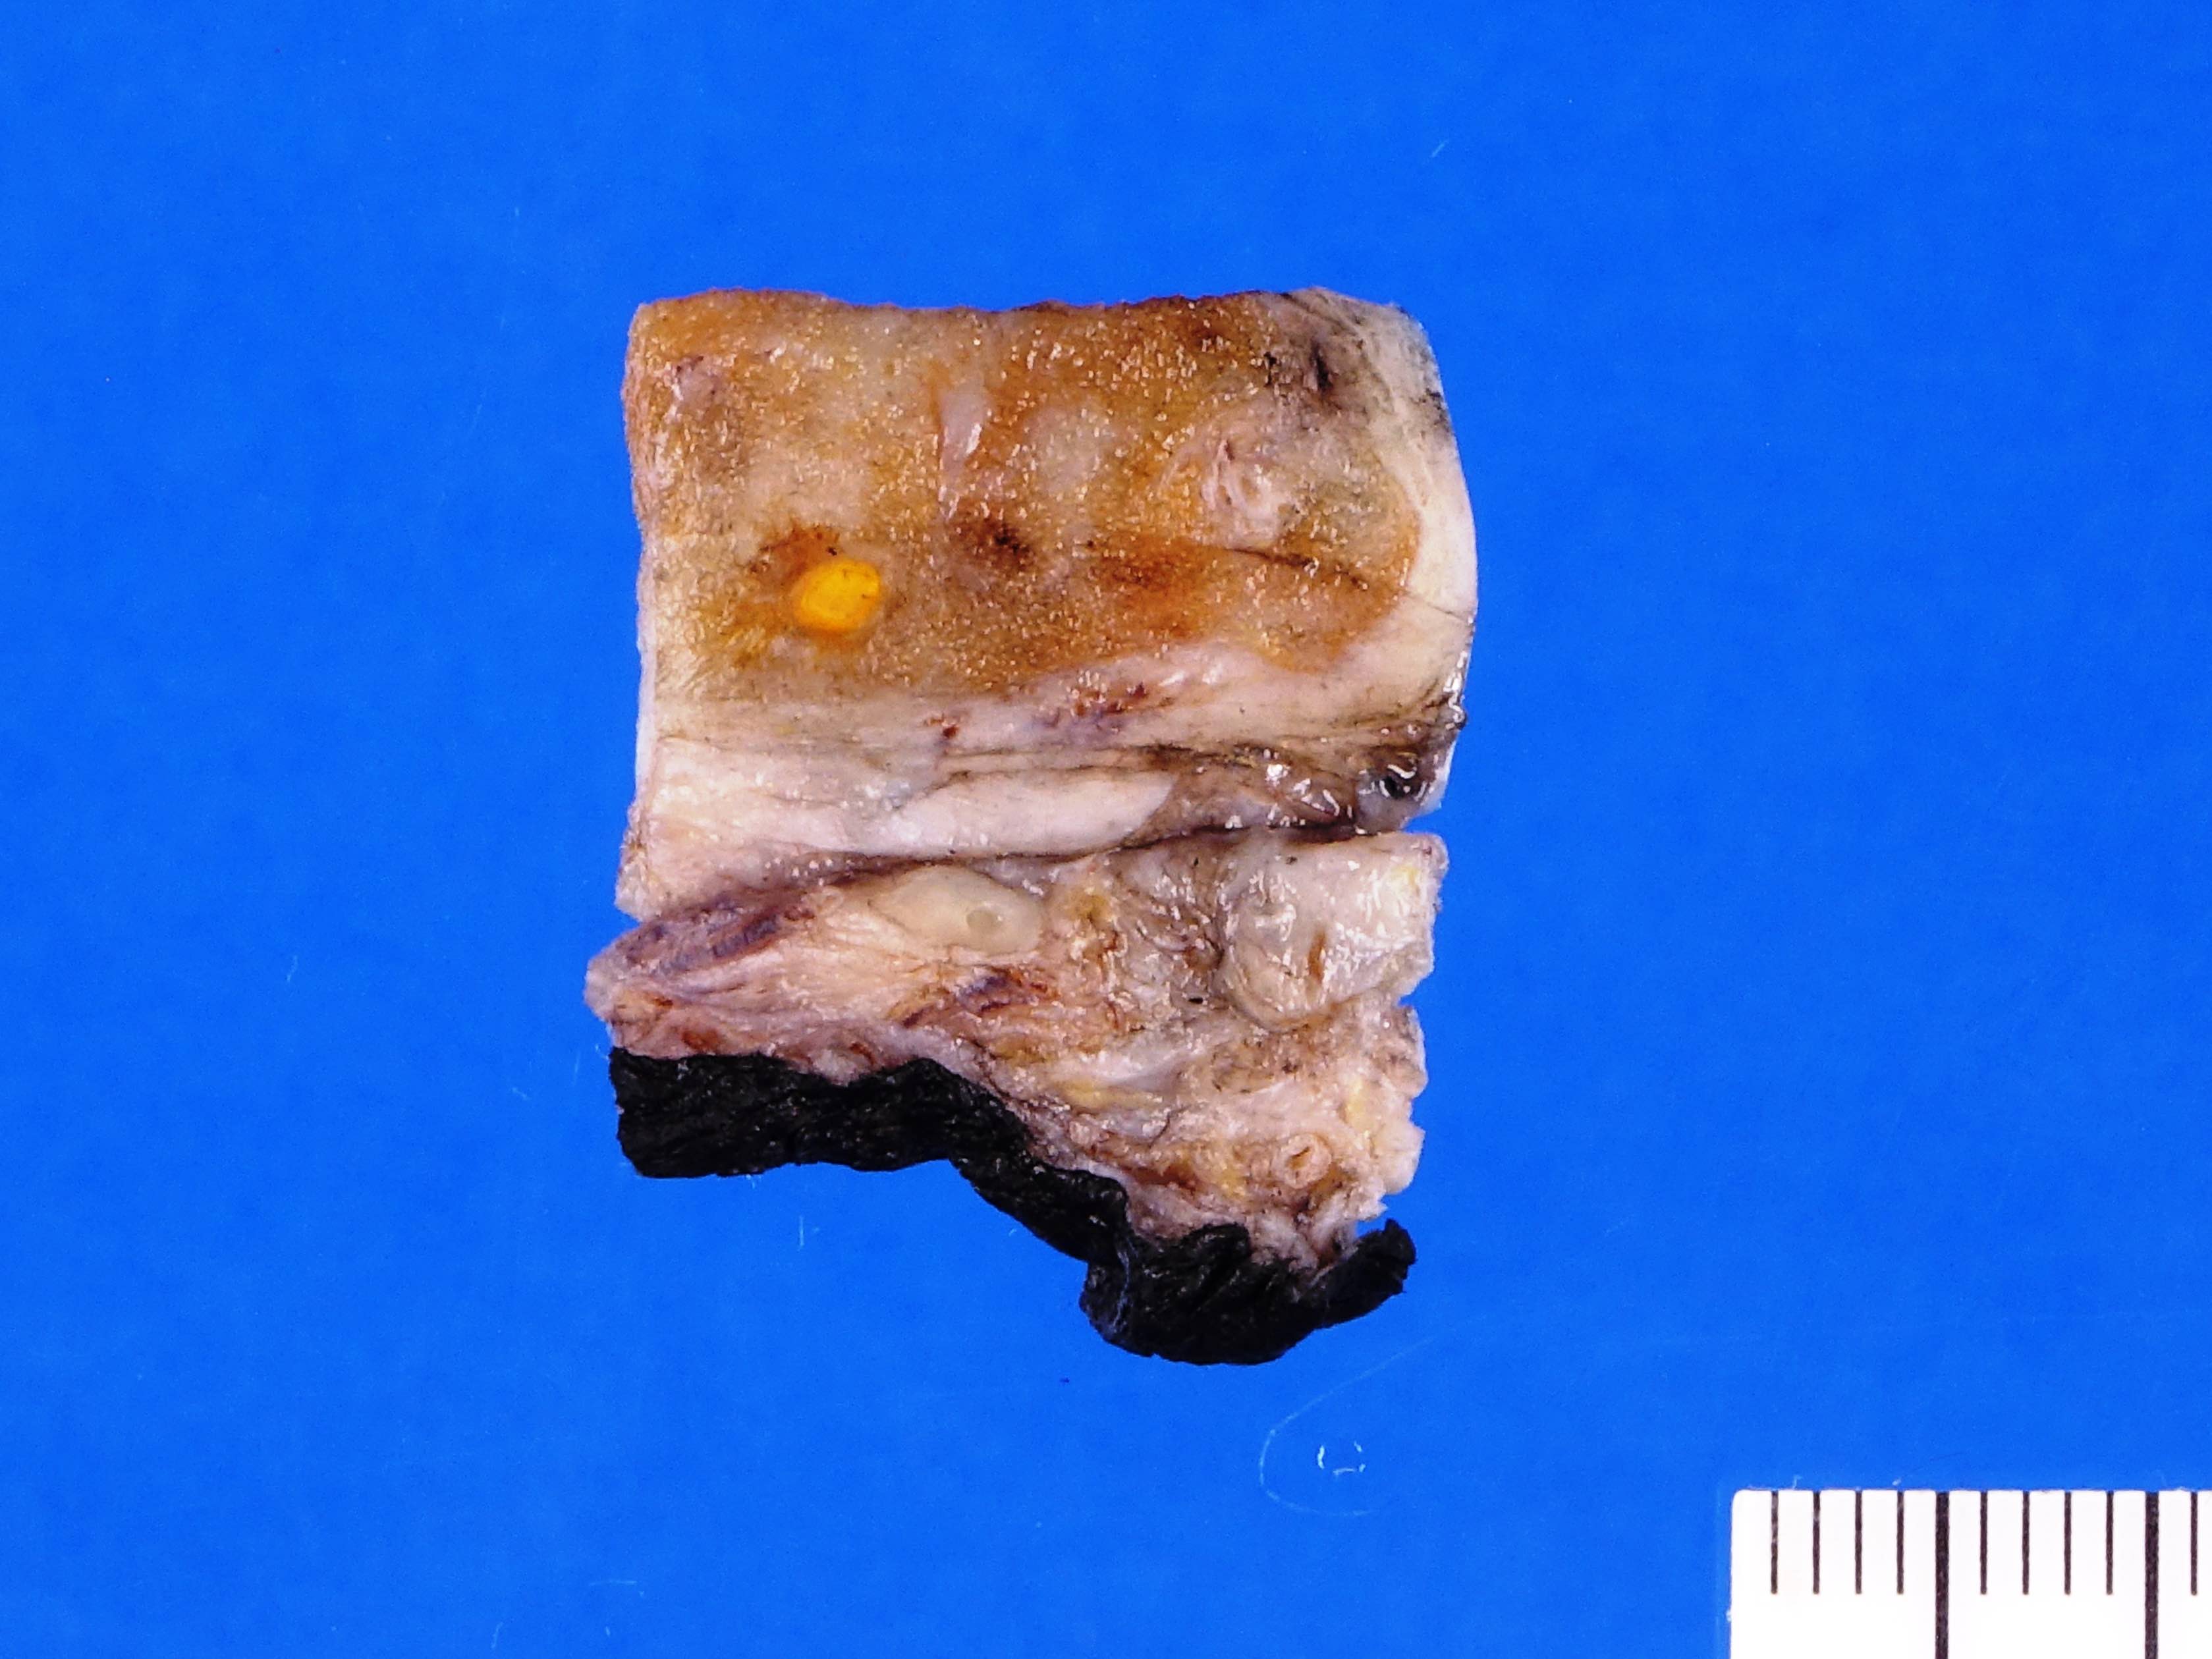

Gross images

Contributed by Debra L. Zynger, M.D.

No residual node tumor (ypN0)

Discontinuous spermatic cord (pM1)